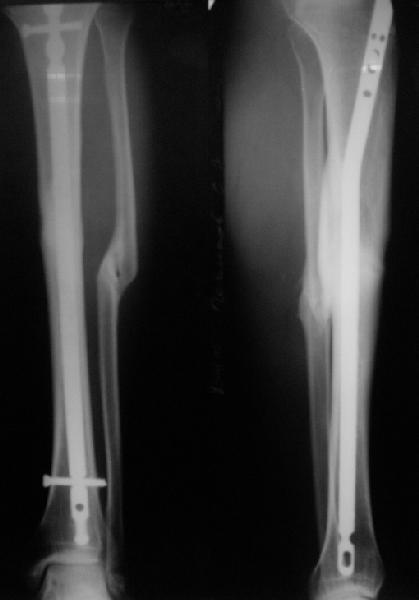

Вот пример, тоже открытый перелом, первичный дефект, пробыл в аппарате 5 мес. Титановый гвоздь, сразу динамический, без покрытия. Больше не делали ничего.

Внедрение одного отломка в другой приведет к укорочению. Резекция с выращиванием резко удлинит срок лечения, вероятно, потребуются еще какие-то операции после завершения дистракции... А самое главное, это избыточные действия. Ведь дефект не сегментарный, краевой контакт есть.

Вполне достаточно закрытого интрамедуллярного остеосинтеза без открытых вмешательств в зоне стыка. Конечно, с рассверливанием. Если есть опасения насчет инфекции, то на гвоздь нанести цемент с ванкомицином.

Гвоздь тут будет эндопротезом диафиза на достаточное время для образования сращения в зоне имеющегося небольшого контакта. И далее страховкой от рефрактур.